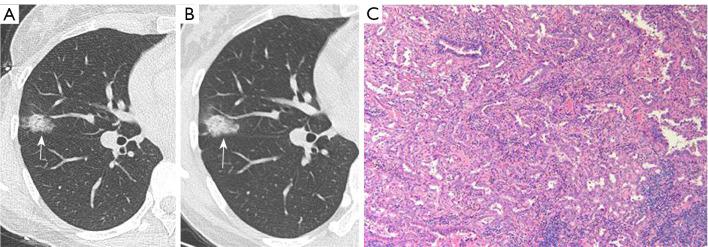

Different pathological stages of lung adenocarcinoma require different surgical strategies and have varying prognoses. Predicting their invasiveness is clinically important. This study aims to develop a nomogram to predict the invasiveness of lung adenocarcinoma manifesting as ground-glass nodules (GGNs) based on follow-up computed tomography (CT) imaging.

METHODS

We retrospectively collected data of 623 GGNs from 601 patients who underwent two follow-up chest CT scans and were confirmed as lung adenocarcinoma by postoperative pathology between June 2017 and August 2023. These patients were randomly divided into training and testing sets in a 7:3 ratio. Eighty-seven GGNs from 86 patients who underwent surgery between September 2023 and April 2024 were prospectively collected as a validation set. The volume, mean density, solid component volume (SV), percentage of solid component (PSC), and mass of GGNs were evaluated using the InferRead CT Lung software. Patients were classified into Group A (atypical adenomatous hyperplasia, adenocarcinoma in situ, and minimally invasive adenocarcinoma) and Group B (invasive adenocarcinoma). Three predictive models were established: model 1 utilized clinical characteristics and morphological features on pre-surgical CT, model 2 incorporated clinical characteristics, morphological features and quantitative parameters on pre-surgical CT, and model 3 utilized all selected features on baseline and pre-surgical CT.

肺腺癌的不同病理阶段需要不同的手术策略,且预后各异。预测其侵袭性在临床上具有重要意义。本研究旨在基于随访计算机断层扫描(CT)影像开发一种列线图,以预测表现为磨玻璃结节(GGN)的肺腺癌的侵袭性。

方法

我们回顾性收集了2017年6月至2023年8月期间601例接受两次胸部CT随访扫描且术后病理确诊为肺腺癌的患者的623个GGN数据。这些患者按7:3的比例随机分为训练集和测试集。前瞻性收集了2023年9月至2024年4月期间86例接受手术的患者的87个GGN作为验证集。使用InferRead CT Lung软件评估GGN的体积、平均密度、实性成分体积(SV)、实性成分百分比(PSC)和质量。患者分为A组(非典型腺瘤样增生、原位腺癌和微浸润腺癌)和B组(浸润性腺癌)。建立了三种预测模型:模型1利用术前CT的临床特征和形态学特征,模型2纳入术前CT的临床特征、形态学特征和定量参数,模型3利用基线和术前CT上所有选定的特征。